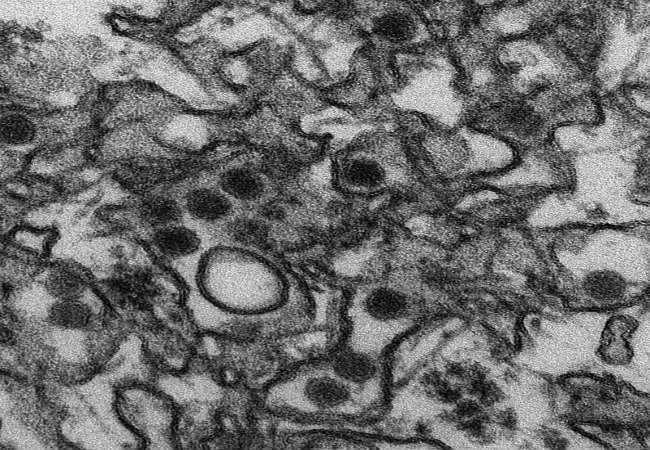

साओपाउलो : ब्राजील की राष्ट्रपति ने चिंतित देश से वादा किया है कि जीका वायरस के खतरे से निपटने में कोई कसर नहीं छोडी जाएगी. विश्व स्वास्थ्य संगठन द्वारा मच्छर जनित इस वायरस से फैल रही बीमारी को अंतरराष्ट्रीय इमर्जेन्सी घोषित किये जाने के एक दिन बाद कांग्रेस को संबोधित कर रहीं ब्राजील की राष्ट्रपति दील्मा रौसेफ ने कहा ‘हमें माइक्रोसिफैली के बारे में चिंता होनी चाहिए.’ जीका वायरस के खतरे से निपटने में कोई कसर न छोडने का वादा करते हुए दील्मा ने कांग्रेस से आह्वान किया कि वह इस वायरस के खिलाफ अभियान में उनका साथ दे.

ब्राजील में गर्भवती माताओं को जीका वायरस का संक्रमण होने की वजह से उनके बच्चों के मस्तिष्क में विकृति आ गयी है और उनके सिर असामान्य रूप से छोटे भी हैं. अक्तूबर के बाद से ब्राजील में माइक्रोसिफैली के कई मामलों की खबर है. बहरहाल अनुसंधानकर्ता अब तक इसका वायरस से निश्चित संबंध साबित नहीं कर पाए हैं. जीका के लिए फिलहाल कोई टीका या दवा नहीं है. ब्राजील में अगस्त से रियो डी जेनेरियो में ओलंपिक खेलों की शुरुआत होनी है. जिन जल निकायों में प्रतियोगिताएं होनी हैं वहां बैक्टीरिया और वायरस का स्तर उच्च होने की खबरों के बाद खिलाडियों की सुरक्षा को लेकर सवाल उठने लगे हैं.